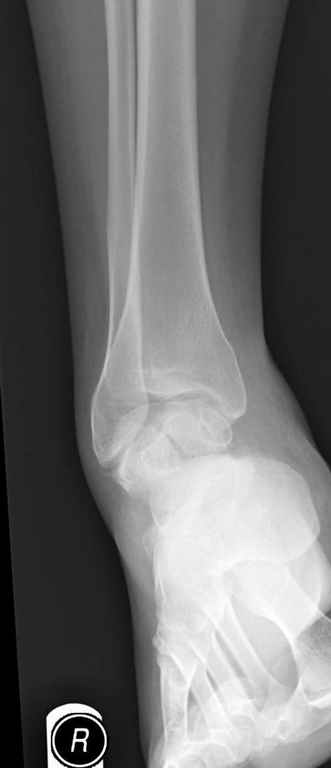

Вдогонку по поводу перелома таранной кости, больная 81, не страдает диабетом, перелом закрытый, в первый же день поступления ограничились временным наружным фиксатором (как на снимке).

Планировалась открытая фиксация после спадения отека, но больная пожелала лечиться по месту жительству в другом штате..

За пару недель насчитал 5 больных с переломом таранной кости, из них двое с двусторонним повреждением.

Из-за отека на стопе тактика лечения у всех была

одинаковая: временная наружная фиксация до спадения отека, при изолированных переломах они выписывались домой и через дней 7 госпитализировались на оперативное лечение.

Примеры на снимке...